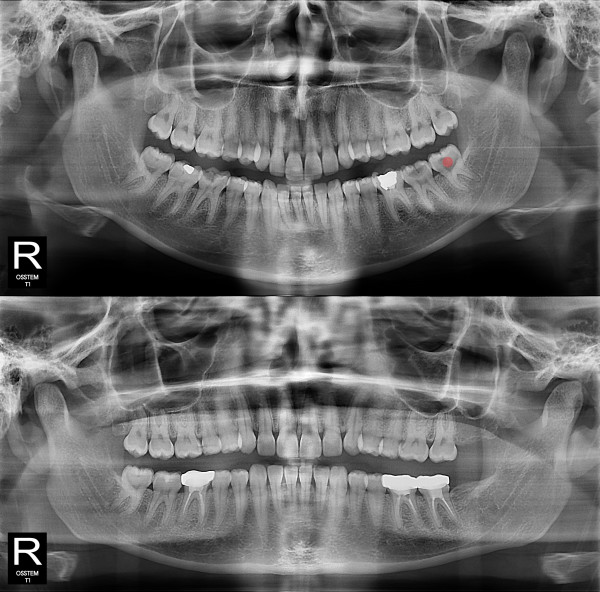

사랑니발치 충치가 심한 사랑니

98c9148a81c37bd910ebd0e3dd27d654_1764731428_909.jpg

98c9148a81c37bd910ebd0e3dd27d654_1764731439_4538.jpg